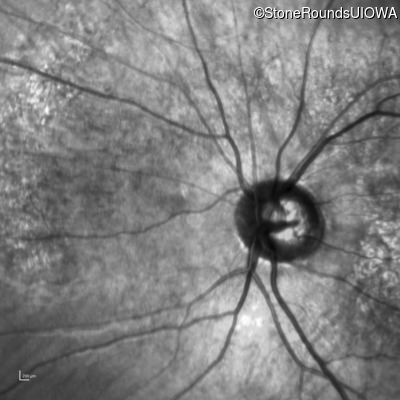

Infrared Fundus Photograph - Right - 10/200

Exemplar

Infrared Fundus Photograph - Left - 10/160 -1